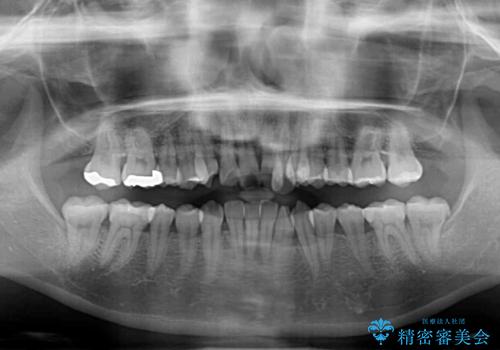

前歯のデコボコが顕著なのはもちろんですが、左右ともに奥歯の咬み合わせに問題があり、上顎臼歯が前方位にある状態でした。

上顎は左右の第一小臼歯2本を、下顎は左右第二小臼歯2本を抜歯することで、奥歯の咬み合わせを改善しながら、デコボコを解消していくこととしました。